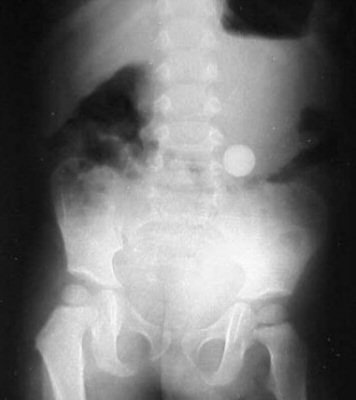

| Figure 11 |

In figure 11 we have a KUB image of a 24-month-old who has swallowed a marble that is in the process of passing through his GI tract.